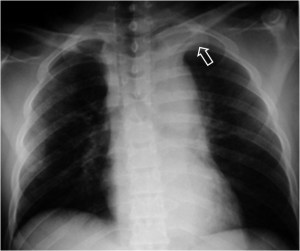

SIGNO DEL CASQUETE APICAL IZQUIERDO

La aparición de una densidad en el ápex pulmonar izquierdo, de borde inferior cóncavo y bien delimitado (casquete apical) en un paciente con traumatismo torácico, debe hacernos sospechar la existencia de una rotura aórtica.

Deben excluirse otras causas de casquete apical, especialmente las lesiones residuales tuberculosas, que suelen acompañarse de otros hallazgos como tractos fibrosos pleuro-parenquimatosos, pérdida de volumen en el lóbulo superior, granulomas, etc.

Mostramos un caso de rotura aórtica por accidente de moto. En este paciente también aparece el signo de la alteración del contorno aórtico.